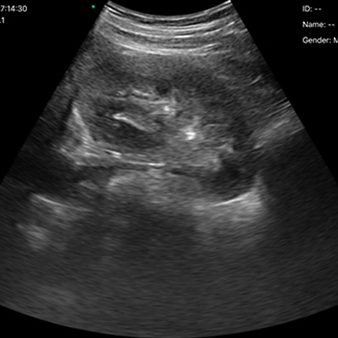

El escáner de ultrasonido portátil de doble sonda es una solución avanzada diseñada para ofrecer máxima versatilidad clínica en un solo dispositivo. Gracias a su tecnología integrada, combina tres modos de escaneo —convexo, lineal y phased array— permitiendo evaluar estructuras profundas, tejidos superficiales y realizar estudios cardíacos con alta precisión. Esta integración reduce significativamente los costos al reemplazar la necesidad de adquirir múltiples sondas por separado.

Abdomen

-

Cardíaco

-

Pulmonar

-

Vascular

-

Obstetricia